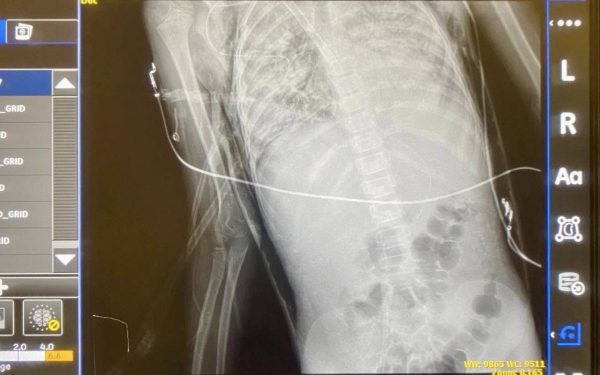

Проте через ускладнення дитину госпіталізували в місцеву лікарню – у неї розвинулася важка деструктивна пневмонія, ускладнена пневмотораксом. Медики провели оперативне втручання та невдовзі перевели пацієнтку на штучну вентиляцію легень, проте стан дівчинки продовжував погіршуватись.

На фоні важкої двобічної пневмонії зберігався високий витік повітря з легень у плевральну порожнину (пневмоторакс), сформувалась підшкірна емфізема. Забезпечити організм достатнім рівнем киснем за допомогою стандартних методів майже не вдавалось, а транспортувати дитину було неможливо через стрімке зниження рівня кисню у крові та прогресування гемодинамічної нестабільності. У медиків залишалося зовсім мало часу. Тоді на допомогу прийшли спеціалісти НДСЛ “Охматдит”.

«Стан легень був критичним: вони не вентилювалися через тотальне ураження та витік повітря, яке продовжувало виходити у плевральну порожнину. Легені були настільки пошкоджені, що кожна спроба їх роздути призводила до ще більшого витоку. Тому ми зупинили вентиляційну підтримку. Такий метод дає можливість легеням “відпочити” та “злипнутися” природним чином. Це допомогло зупинити витік повітря та стабілізувати стан. Після цього дуже обережно, поетапно, ми почали їх знову роздувати — інакше вони могли б повторно розірватися», – продовжує пояснювати Станіслав Школьний.

За час лікування дівчинці кілька разів змінювали дренажі через нові зони пошкодження. Невдозі, після появи ознак відновлення легень, ШВЛ було зупинено та пацієнтку було переведено на самостійне дихання із частковою підтримкою газообміну за допомогою ЕКМО (awake ECMO). У кінцевому результаті лікарям вдалось відлучити її від екстракорпоральної підтримки. Потім — тривалий процес реабілітації, який починався ще на ЕКМО. Далі дитину перевели у відділення торакальної хірургії, де лікарі-хірурги продовжили процес лікування деструкції із кінцевим позитивним результатом. Кожен крок у цій історії був зваженим і складним. Але сьогодні Каріна нарешті готується до довгоочікуваної виписки.